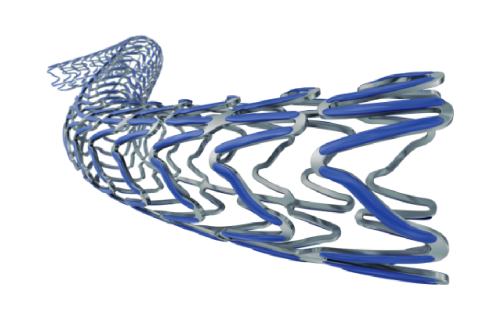

Na área de Cardiologia Intervencionista, fornecemos dispositivos de ponta, como stents, cateteres e balões, que são essenciais para a realização de angioplastias e outros procedimentos cardíacos minimamente invasivos. Nossos produtos são projetados para oferecer máxima eficiência e segurança, contribuindo para a rápida recuperação dos pacientes e a redução de complicações pós-operatórias.

Nossa atuação em Neurorradiologia Intervencionista inclui a oferta de microcateteres e stents especializados para o tratamento de aneurismas cerebrais e outras condições neurológicas críticas. Esses dispositivos são desenvolvidos com tecnologia de ponta para garantir a máxima segurança e eficácia durante os procedimentos, ajudando a preservar a integridade cerebral dos pacientes.